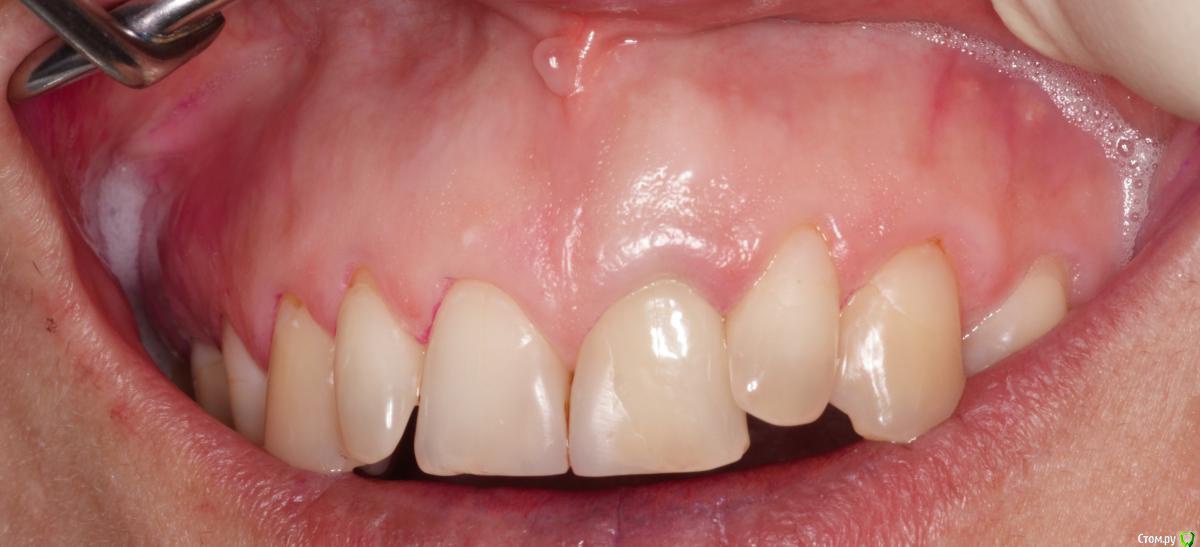

skeettrap Опубликовано 7 июня, 2016 Автор Поделиться Опубликовано 7 июня, 2016 (изменено) Наконец пациентка дошла. Пока все нормально и свищ не появлялся больше. Зуб 21. Изменено 7 июня, 2016 пользователем skeettrap 3 Ссылка на комментарий